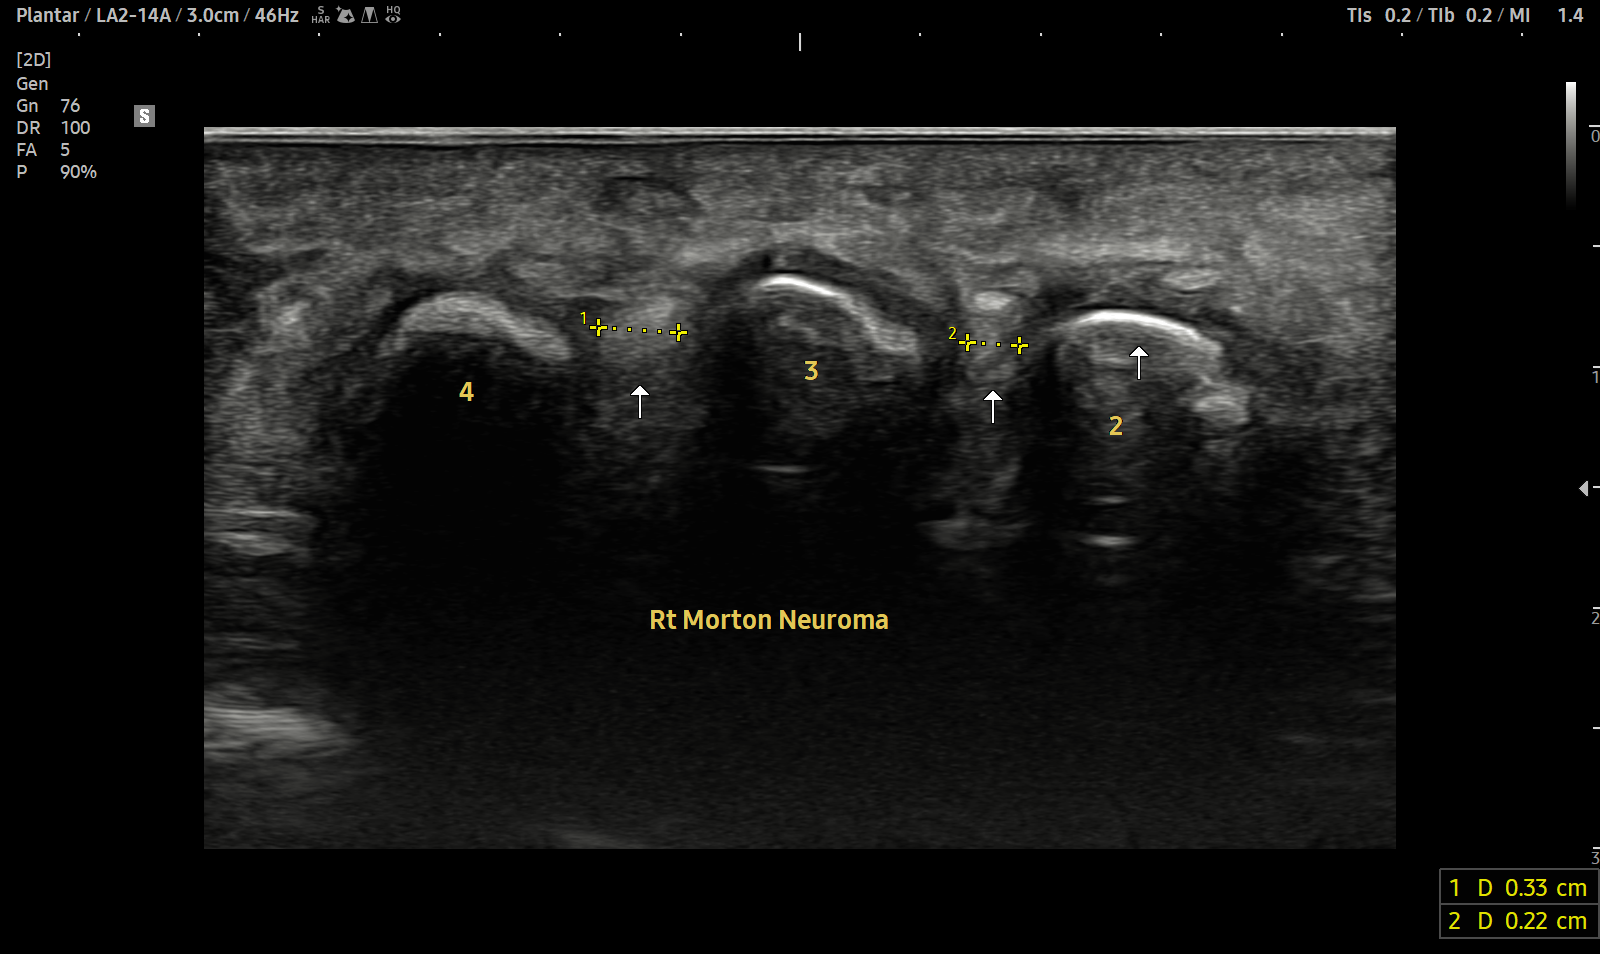

- 치료기간 : 25 . 4 . 1 ~ 25 . 5 26.

- 치료횟수 : 19 회

치료 전

치료 후